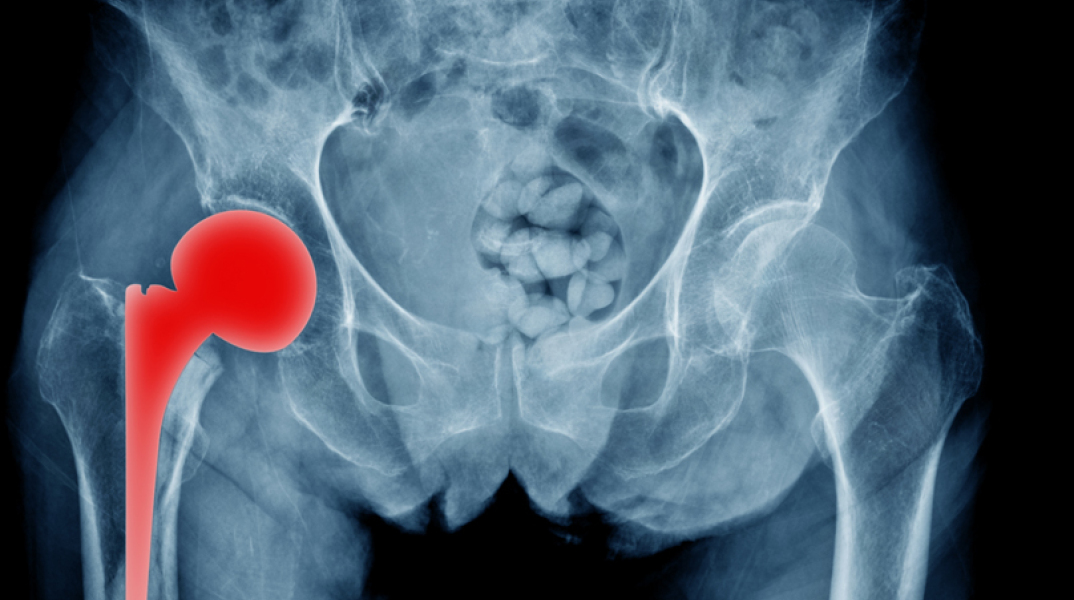

Η τεχνική Super PATH για την ολική αρθροπλαστική ισχίου

Μια επέμβαση που κατά κύριο λόγο εφαρμόζεται ως τελική θεραπευτική λύση για την αντιμετώπιση της οστεοαρθρίτιδας του ισχίου είναι η ολική αρθροπλαστική. Η οστεοαρθρίτιδα γενικά αποτελεί μια εκφυλιστική νόσο των αρθρώσεων που επιφέρει πόνο και περιορισμό της κινητικότητάς τους. Αυτά τα συμπτώματα μπορεί να είναι τόσο έντονα που να οδηγήσουν ακόμα και σε αδυναμία εκπλήρωσης καθημερινών δραστηριοτήτων ρουτίνας.

Ολική αρθροπλαστική ισχίου

Η ολική αρθροπλαστική του ισχίου βελτίωσε και συνεχίζει να βελτιώνει την ποιότητα ζωής εκατομμυρίων ασθενών εδώ και δεκαετίες. Ωστόσο, για μεγάλο χρονικό διάστημα παρέμενε μια βαριά, συχνά αιμορραγική επέμβαση που απαιτούσε μακρά νοσηλεία και αποκατάσταση. Στην πορεία των ετών η ορθοπαιδική χειρουργική εξελίχθηκε επιστημονικά και ταυτόχρονα εξελίχθηκε και η επιστήμη των υλικών που χρησιμοποιούνται στα χειρουργεία. Αποτέλεσμα αυτών των εξελίξεων αποτελούν οι νέες χειρουργικές τεχνικές που εντάσσονται στο χειρουργικό οπλοστάσιο του ορθοπαιδικού χειρουργού για την αντιμετώπιση της οστεοαρθρίτιδας του ισχίου.

Τεχνική Super PATH

«Την τελευταία πενταετία στο Metropolitan Hospital υιοθετήθηκε στην καθημερινή χειρουργική πράξη η τεχνική Super PATH, μια σύγχρονη, εξελιγμένη τεχνική ολικής αρθροπλαστικής ισχίου με προσπέλαση ελάχιστης επεμβατικότητας, η οποία συνοδεύεται από επιστημονικά δεδομένα τεκμηρίωσης στη διεθνή βιβλιογραφία.

Στόχος της συγκεκριμένης χειρουργικής τεχνικής ελάχιστης επεμβατικότητας είναι η αντικατάσταση της άρθρωσης υπό συνθήκες μέγιστης προστασίας των μαλακών μορίων της περιοχής της άρθρωσης του ισχίου. Αυτό σημαίνει ότι πρώτιστο ζητούμενο αυτής της επέμβασης είναι το λειτουργικό αποτέλεσμα, ενώ το αισθητικό αποτέλεσμα που, μερικές φορές, προτάσσει ο ασθενής, παρανοώντας το συνολικό νόημα της επέμβασης, εξαρτάται από το μέγεθος της τομής που γίνεται για την προσπέλαση της περιοχής. Συνεπώς, γίνεται μεν η προσπάθεια η τομή να είναι η ελάχιστη δυνατή, καθώς αυτή είναι η άμεση εικόνα που έχει ο ασθενής από το χειρουργείο, ωστόσο δεν γίνεται αντικατάσταση άρθρωσης με εισαγωγή υλικών χωρίς την ύπαρξη επαρκούς τομής. Η τομή είναι τόση ώστε να επιτευχθεί η μέγιστη προστασία των μαλακών μορίων και των τενόντων της περιοχής που αποτελεί την προϋπόθεση για την πρώιμη κινητοποίηση του ασθενούς, το μεγαλύτερο εύρος κίνησης της άρθρωσης και την ελαχιστοποίηση του μετεγχειρητικού πόνου», εξηγεί ο ιατρός.